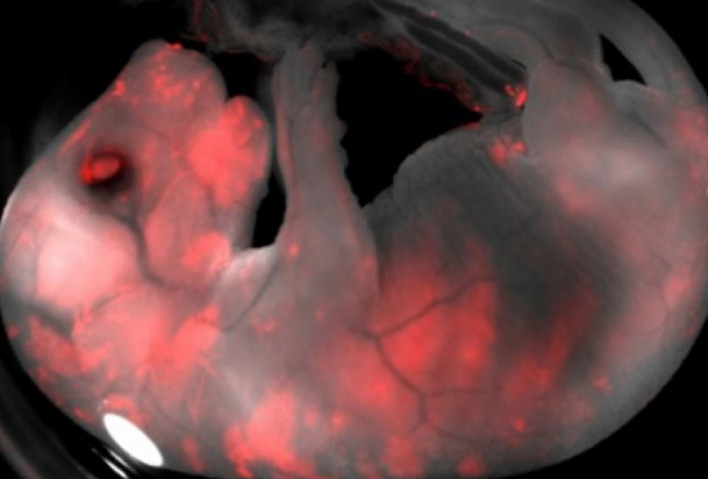

Ինչպես տեղեկացնում է NATURE News-ը ,  ամերիկացի, իսպանացի եւ ճապոնացի կենսաբաններն ստեղծել են քիմեռներ՝ խոզի եւ մարդու հիբրիդներ,որը հրապարակվել է Cell հանդեսում: Գիտնականները խոզի ավելի քան 1,4 հազար սաղմեր մտցրել են մարդու մակածված ցողունային բջիջների երեք տիպերից մեկում: Այնուհետեւ սաղմերը պատվաստվել են մայր խոզին, որտեղ դրանք հաջողությամբ զարգացել են: Մարդկային նյութի դինամիկային հետեւել են ֆլուորեսցենտային սպիտակուցի միջոցով, որի արտադրության համար ծրագրավորվել էին մարդու ցողունային բջիջներ: Վերջինները խոզի սաղմում ձեւավորել են բջիջներ, որոնք տարբեր տեսակի հյուսվածքների, մասնավորապես, սրտի, լյարդի եւ նյարդային համակարգի հյուսվածքների նախորդներ են: Խոզի եւ մարդու հիբրիդներին թույլ են տվել զարգանալ երեք-չորս շաբաթվա ընթացքում, ինչից հետո Էթիկական նկատառումներով դրանք ոչնչացվել են:

Գիտնականներն իրենց փորձերի վերջնական նպատակը տեսնում են այնպիսի օրգանների աճեցման արդյունավետ մեթոդիկայի մշակման մեջ, որոնք հետագայում պիտանի կլինեն հիվանդին փոխպատվաստելու համար: